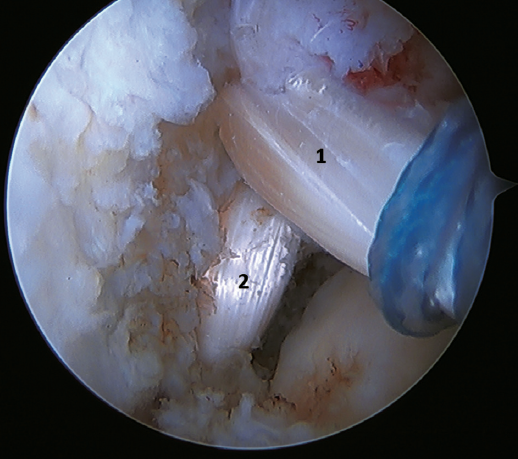

The main indication for this repair is rupture of the upper fascicle of the ATFL from its fibular insertion, with good tissue quality of the remaining ligament (Figure 3).

The technique can be performed through a single modified anterolateral portal or using a third accessory portal. The use of a single portal reduces the risk of injury to the intermediate dorsal cutaneous branch of the superficial peroneal nerve(37). Although there is no difference between the use of one or two implants, the use of two implants implies a larger contact surface(38,39) and improves patient incorporation to sports activities(40,41,42,43,44).